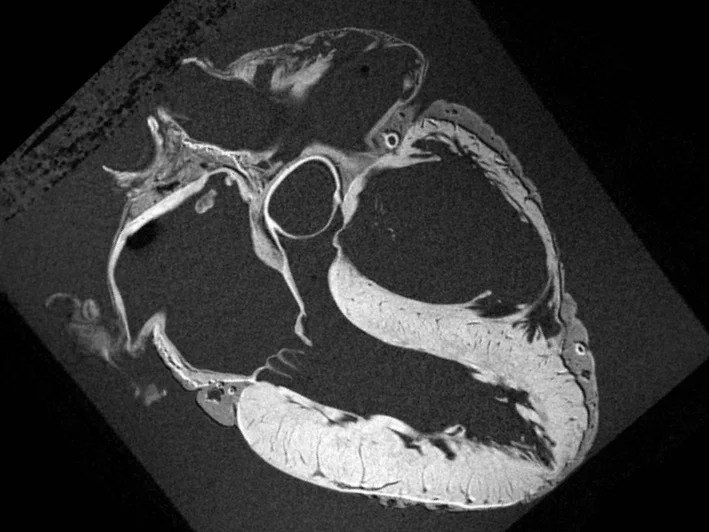

МРТ серця – це високоточний неінвазивний метод діагностики, що використовується для оцінки стану серцевого м'яза, клапанів, судин та інших структур серцево-судинної системи. Магнітно-резонансне дослідження дозволяє виявляти різні патології, включаючи ішемію, інфаркти, аневризми, фіброз та інші зміни в серці, які можуть бути не видні за допомогою інших методів обстеження.

МРТ серця — це метод, який використовує магнітне поле та радіочастотні імпульси для створення детальних зображень серцевих структур. Процедура дозволяє не лише виявляти патології, а й оцінювати функціональний стан серцевого м'яза, а також визначати ступінь кровотоку та наявність ушкоджень у серцевих тканинах.

МРТ серця дає можливість детально оцінити морфологію серця, його функціональні характеристики та стан перикарда. Процедура є абсолютно безпечною, оскільки не передбачає використання рентгенівського випромінювання і підходить для обстеження пацієнтів різного віку, включаючи вагітних жінок, новонароджених і людей з різними імплантами.

МРТ серця дозволяє отримати зображення, яке точно і детально показує не тільки серцеві тканини, а й інші важливі структури, такі як судини, клапани та перикард. МРТ серця покаже:

- інфаркти, ішемію та набряк міокарда;

- фіброзні зміни в міокарді;

- наявність аневризм серця;

- структурні зміни серцевого м'яза;

- пухлини та зміни в аорті та великих судинах.

Також дослідження показує ступінь кровотоку в серці та оцінку функції серцевого м'яза. МРТ серця є надзвичайно корисним для діагностики не тільки серцевих захворювань, але й для виявлення новоутворень і аневризм.